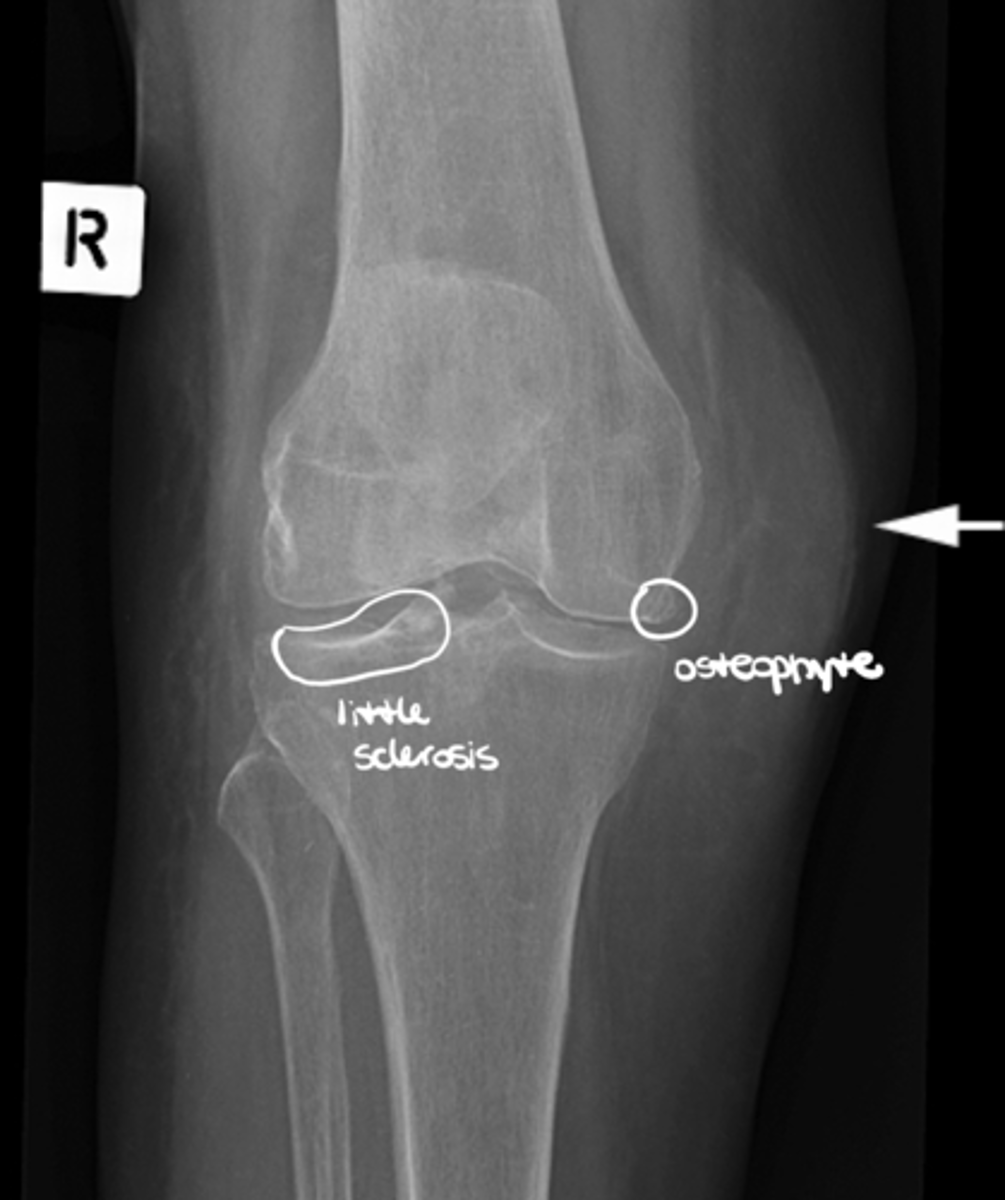

What is sclerosis?

Hardening of the bone tissue at the joint line (often a primary indicator of OA)

If we identify a loss of joint space on a plain film radiograph, what may this imply?

Loss of cartilage (primary indication of OA, along with bone spurs and sclerosis)

List the sub-components of (A) alignment: general contour

- Spurs and osteophytes